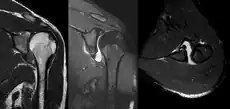

A diagnosis of shoulder dislocation is often suspected based on the person's history and physical examination. Radiographs are made to confirm the diagnosis. Most dislocations are apparent on radiographs showing incongruence of the glenohumeral joint. Posterior dislocations may be hard to detect on standard AP radiographs, but are more readily detected on other views. After reduction, radiographs are usually repeated to confirm successful reduction and to detect bone damage. After repeated shoulder dislocations, an MRI scan may be used to assess soft tissue damage. In regards to recurrent dislocations, the apprehension test (anterior instability) and sulcus sign (inferior instability) are useful methods for determining predisposition to future dislocation.

A Hill–Sachs lesion is an impaction of the head of the humerus left by the glenoid rim during dislocation.[6] Hill-Sachs deformities occur in 35–40% of anterior dislocations. They can be seen on a front-facing X-ray when the arm is in internal rotation.[9] Bankart lesions are disruptions of the glenoid labrum with or without an avulsion of bone fragment.